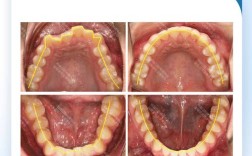

• 牙齿矫正器矫正牙齿的具体步骤和原理是什么?

牙齿矫正器矫正牙齿的具体步骤和原理是什么?

牙齿矫正器的核心原理是通过持续、轻柔的生物力学力,引导牙齿在牙槽骨内缓慢移动,最终排列整齐、咬合协调,这一过程基于“牙槽骨改建”机制:当牙齿受到适当外力时,受力侧牙槽骨会被吸收,另一侧则增生,牙齿随之移动至新位置,同时牙周组织(牙周膜、牙龈...